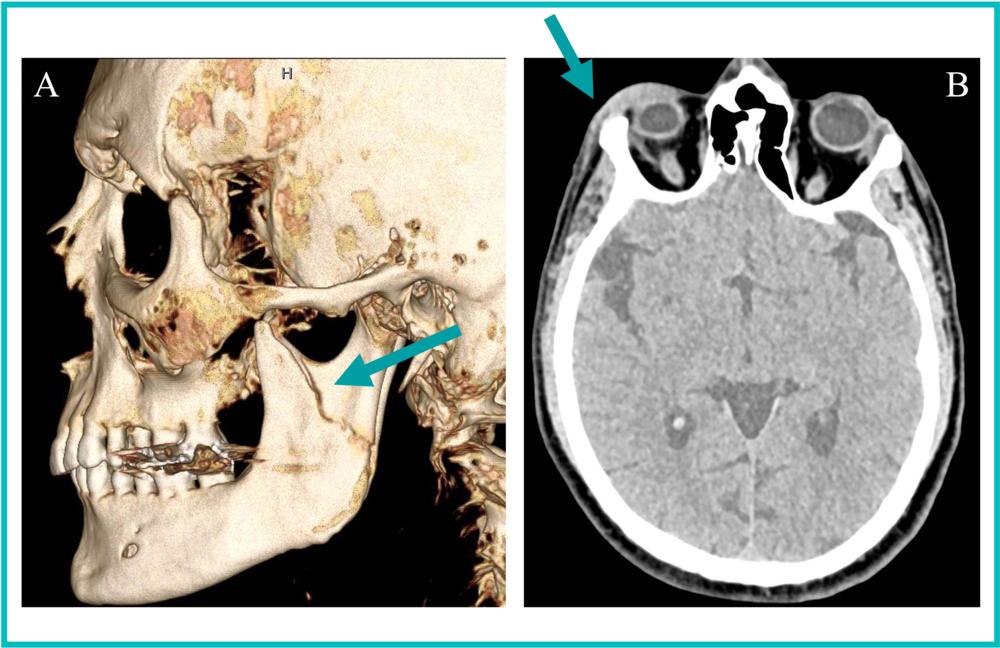

Figure 1. 35-year-old transgender woman presents with (A) a 3D CT reformation of the face in the sagittal plane showing a left mandibular fracture (arrow). (B) An axial head CT image from one of three head CT studies over the last two years revealing right periorbital soft tissue swelling (arrow). The radiologist reader suspected intimate partner violence based on radiology reports, which was subsequently confirmed through clinical note examination.